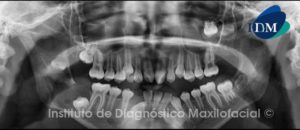

Paciente 61 años de edad, sexo masculino, es referido a la consulta radiológica para la colocación de implantes dentales en el maxilar inferior.